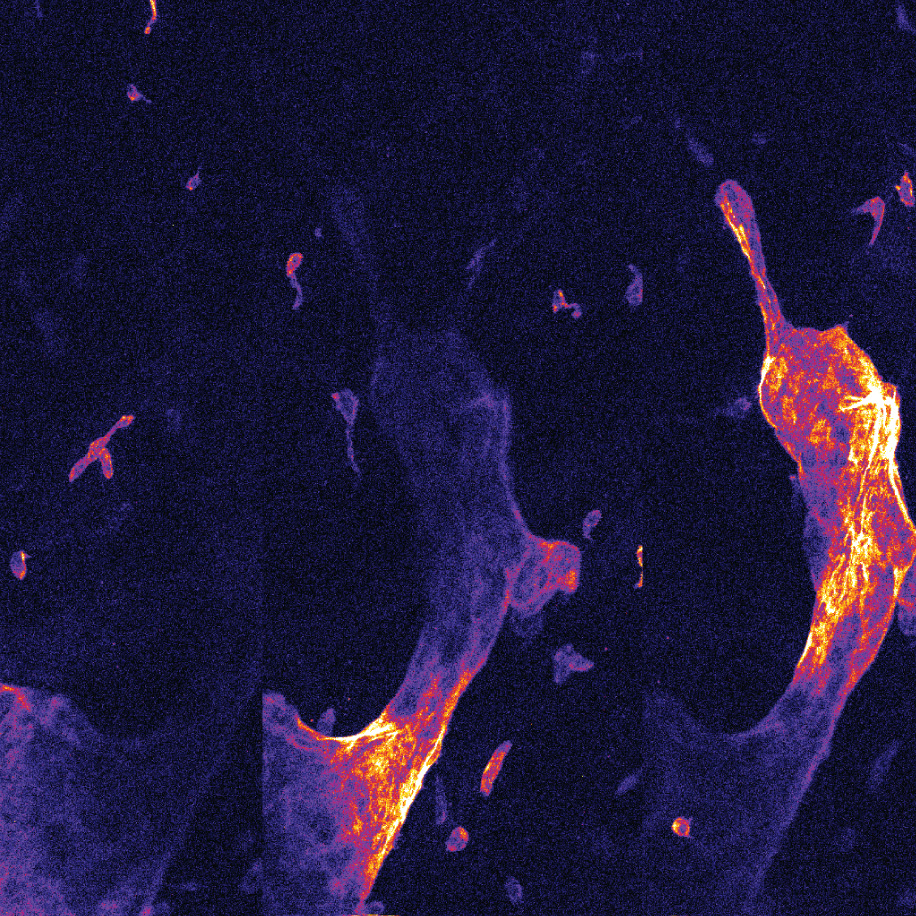

Images can be easily post-processed to produce a range of presentations (incl 3D).

Photodynamic Therapy (PDT) |

| Microvascular research |

Molecular Imaging |